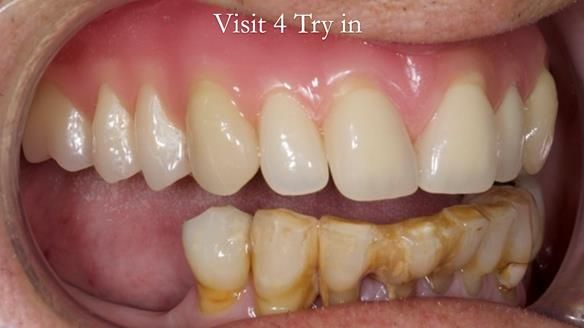

Welcome to my Newsletter 54 showing the making and fitting of dentures (a complete upper metal reinforced denture, a lower immediate partial denture and a definitive Scandinavian designed, metal based lower partial denture) for David, a 75 -year-old man. The full protocol workflow is presented including the use of dentate photographs to mimic his natural teeth.

The clinical situation and treatment process is shown in detail below. I provided the clinical work. Rowan Garstang, my dental technician, provided the technical work.

Interestingly we found that the upper complete denture when finished and fitted didn’t have good enough retention for David’s satisfaction. It was relined by adding compound to the buccal flanges – to almost overextend into the sulcus to ‘create’ a sulcus, followed by using a light bodied silicone impression material. This improved the function of the C/-considerably. A lower Scandinavian hygienically designed lower RPD was also provided which helped with occlusal stability and reseating the upper denture – further improving the fit.